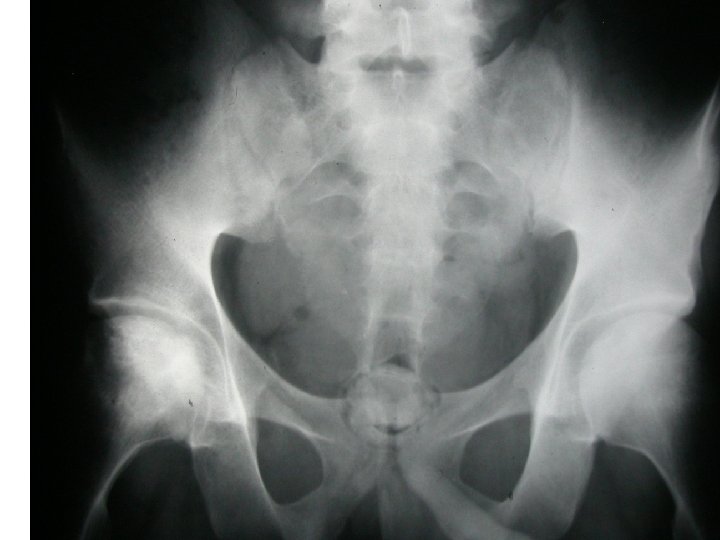

SEMIOLOGIE DE LA HANCHE J-P ESCHARD • Anatomie Articulation profonde Articulation très emboîtée mobilité

SEMIOLOGIE DE LA HANCHE J-P ESCHARD • Anatomie Articulation profonde Articulation très emboîtée mobilité réduite